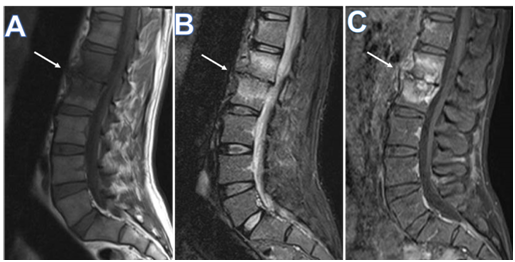

Figure 2 Sagittal MRI of the lumbosacral spine, (A) T1 weighted, (B) T2 weighted, and (C) T1-fat saturated post I.V. gadolinium based contrast medium, showing spondylodiscitis involving Lumbar vertebral bodies L1 and L2, and interposed intervertebral disc, a central pattern with disc destruction, opposed end plate irregularity (arrows in A, B , and C), and diffuse marrow edema, the latter appearing as low signal on T1W, bright on T2W, and post contrast enhancement. Note, minimal prevertebral subligamentous inflammatory changes, and mild posterior epidural bulge against anterior thecal sac.

A 45-year-old Bangladeshi male working as a livestock farmer in Qatar presented to the emergency department with acute onset of weakness of the right side of the body, requiring assistance for walking. There were no seizures, altered sensorium, or history suggestive of cranial nerve involvement. The patient had a low-grade fever, significant weight loss, and low back pain during the last two months. He was on metformin for newly detected diabetes over the previous four months. On examination, he was febrile with an oral temperature of 38.1 degrees Celsius but otherwise stable. He had right hemiparesis with upper limb power of 2/5 proximally, 3/5 distally, and 2/5 in the right lower limb with hyperreflexia. Other systems were unremarkable. A non-contrast computed tomography (CT) of the brain showed ill-defined small hypodensity in the left corona radiata, which the neurologist decided to treat as acute ischemic CVA. The echocardiogram was unremarkable and ruled out any cardioembolic cause. Given his prolonged constitutional symptoms, specific blood tests for tuberculosis (TB), brucellosis, syphilis, and autoimmune workup were requested, including cerebrospinal fluid (CSF) analysis, magnetic resonance imaging (MRI) of the brain and spinal cord. IgG and IgM serology for B. melitensis and B. abortus were positive (titers >1:80). Blood cultures grew B. canis. MRI Brain and spinal cord showed L1-L2 spondylodiscitis with similar spondylitis like lesions in the superior anterior endplates of T9 and focal right occipital-temporal meningeal enhancement. CSF was unremarkable. TB, Human Immunodeficiency Virus (HIV), syphilis, and autoimmune workup were negative. Ultrasound abdomen showed only a small calcific density within the right lobe of the liver, measuring 4mm. He was treated as a case of neurobrucellosis, given his prolonged symptoms, positive blood culture, and serology, despite normal CSF, with intravenous ceftriaxone 2grams intravenous twice daily for seven days followed by oral doxycycline 100milligrams twice daily and rifampicin 600milligrams daily for three months. After three months of treatment, he had completely recovered from his symptoms when followed up in the infectious diseases’ clinic.